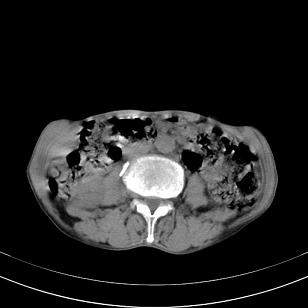

标题: 男,65岁,反复右上腹痛, [打印本页]

标题: 男,65岁,反复右上腹痛,

胃镜提示十二指肠占位